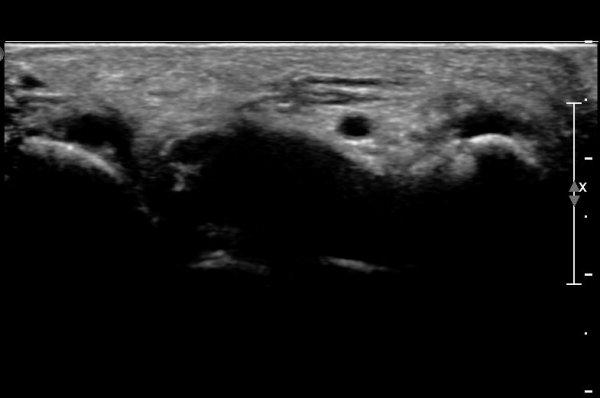

Á¶±Ý ´õ ¸»´ÜÀ¸·Î À̵¿ÇÏ´Ï Äá¾Ë»À ÇÇÁú°ñ ¿¬¼Ó¼º ¼Ò½ÇÀÌ °üÂûµÊ(»çÁö 3),

Äá¾Ë»À Á¾´Ü¸é°Ë»ç¿¡¼­ Äá¾Ë »À ±ÙÀ§ºÎÀÇ ÇÇÁú°ñ °ß¿­ÀÌ °üÂûµÊ(»çÁö 4).